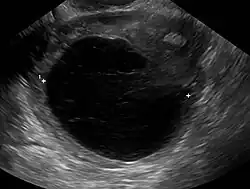

Die Ovarialzyste (Eierstockzyste) ist ein bei Menschen oder Säugetieren in oder an den Eierstöcken gebildeter sackartiger, mit Flüssigkeit unterschiedlicher Konsistenz gefüllter Hohlraum oder eine Geschwulst, die in aller Regel gutartig ist. Sie wächst von einigen Millimetern bis zu über 15 Zentimetern Durchmesser an.

Häufig sind Ovarialzysten nur wenige Zentimeter groß und verursachen keine Symptome. Sie werden in der Ultraschalluntersuchung beim Frauenarzt entdeckt. Moderne Ultraschallgeräte können bereits wenige Millimeter große zystische Veränderungen am Eierstock erkennen, die ungefährlich sind. Nach heutiger Einschätzung handelt es sich bei im vaginalen Ultraschallbild auffälligen Befunden am Eierstock in über 98 Prozent der Fälle um normale Veränderungen, die nicht operiert werden müssen.